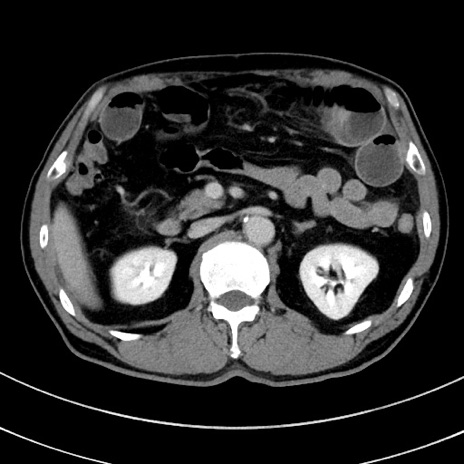

症例8(横断像)

【症例】 60歳代男性

【主訴】 黒色吐物

【現病歴】 4日前から嘔気自覚、2日前の朝食後にも嘔気あり、自分で手で嘔吐反射起こし嘔吐したところ血が混ざっていたため受診。

【既往歴】 5年前汎発性腹膜炎を伴う急性虫垂炎で手術、高血圧、前立腺肥大症、高脂血症

【身体所見】 腹部正中に手術癩痕あり 腹部平坦・軟圧痛なし膨満感あり

【データ】WBC 8400、CRP 4.54